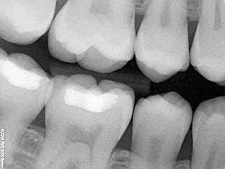

Digital X-Rays

Digital radiography is a form of X-ray imaging, where digital X-ray sensors are used instead of traditional photographic film. Advantages include time efficiency through bypassing chemical processing and the ability to digitally transfer and enhance images. Also less radiation can be used to produce an image of similar contrast to conventional radiography.

Instead of X-ray film, digital radiography uses a digital image capture device. This gives advantages of immediate image preview and availability; elimination of costly film processing steps; a wider dynamic range, which makes it more forgiving for over- and under-exposure; as well as the ability to apply special image processing techniques that enhance overall display of the image.

Digital X-rays can be sent to a computer to be recorded and saved.